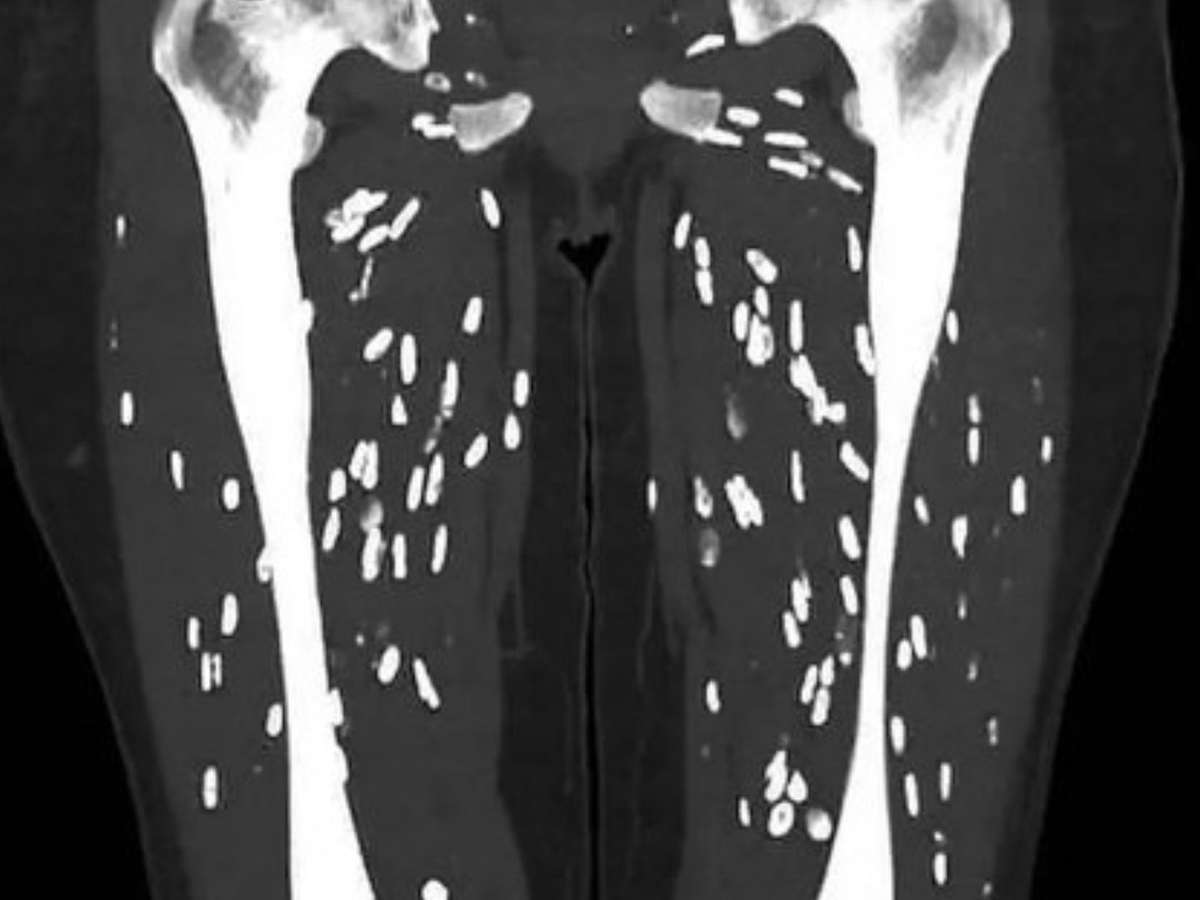

Com mais de seis milhões de visualizações, o médico da Universidade da Flórida, Sam Ghali, levantou um alerta importante nas redes sociais. Utilizando a plataforma X, ele destacou o risco de exposição à cisticercose por meio do consumo de carne de porco mal cozida. Essa condição é causada pelo contato com fezes humanas infectadas pelos ovos da tênia.

O processo de infecção ocorre quando os humanos ingerem esses ovos através de alimentos contaminados, água ou superfícies sujas. Ghali explicou como os cistos da Taenia solium se desenvolvem no corpo humano, podendo levar a sérias complicações se não tratados adequadamente.

Quando os ovos são ingeridos novamente, seja por humanos ou porcos, as larvas penetram na parede intestinal e entram na corrente sanguínea. Elas podem migrar para diversos órgãos do corpo, como cérebro, olhos, tecidos subcutâneos e músculos, onde formam cistos chamados cisticercos.

Exames de imagem, como tomografia computadorizada ou ressonância magnética, são frequentemente utilizados para identificar cisticercos em órgãos como o cérebro ou os olhos. Além disso, testes de laboratório podem detectar anticorpos contra a Taenia solium no sangue.